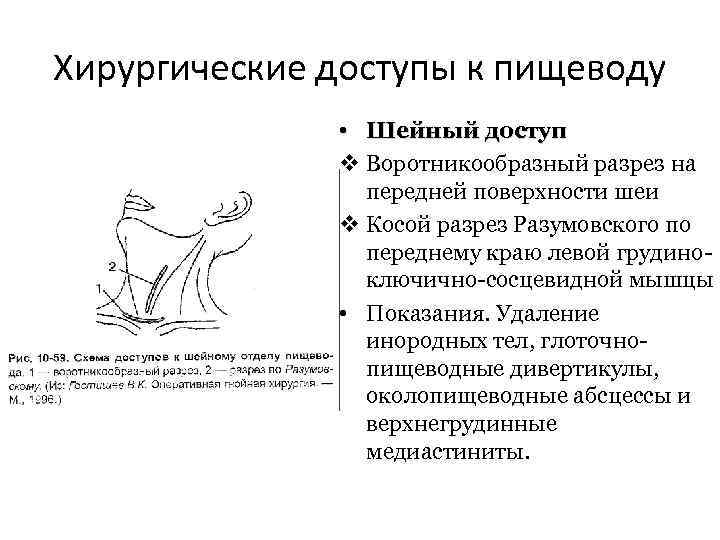

Хирургические доступы к пищеводу • Шейный доступ v Воротникообразный разрез на передней поверхности шеи v Косой разрез Разумовского по переднему краю левой грудиноключично-сосцевидной мышцы • Показания. Удаление инородных тел, глоточнопищеводные дивертикулы, околопищеводные абсцессы и верхнегрудинные медиастиниты.

Хирургические доступы к пищеводу • Шейный доступ v Воротникообразный разрез на передней поверхности шеи v Косой разрез Разумовского по переднему краю левой грудиноключично-сосцевидной мышцы • Показания. Удаление инородных тел, глоточнопищеводные дивертикулы, околопищеводные абсцессы и верхнегрудинные медиастиниты.

• Техника. Больного укладывают на спину с подложенным под плечи валиком, голову запрокидывают и поворачивают вправо. Разрез кожи по переднему краю грудино-ключичнососцевидной мышцы от вырезки грудины до уровня верхнего края щитовидного хряща. Послойно рассекают кожу, подкожную клетчатку, поверхностную фасцию шеи, подкожную мышцу шеи, влагалище грудино-ключично-сосцевидной мышцы вскрывают вблизи переднего края, мышцу оттягивают крючком Фарабефа латерально. Рассекают внутреннюю пластинку грудино-ключично -сосцевидной мышцы и лопаточно-ключичную фасцию шеи.

• Техника. Больного укладывают на спину с подложенным под плечи валиком, голову запрокидывают и поворачивают вправо. Разрез кожи по переднему краю грудино-ключичнососцевидной мышцы от вырезки грудины до уровня верхнего края щитовидного хряща. Послойно рассекают кожу, подкожную клетчатку, поверхностную фасцию шеи, подкожную мышцу шеи, влагалище грудино-ключично-сосцевидной мышцы вскрывают вблизи переднего края, мышцу оттягивают крючком Фарабефа латерально. Рассекают внутреннюю пластинку грудино-ключично -сосцевидной мышцы и лопаточно-ключичную фасцию шеи.

• Левую долю щитовидной железы вместе с трахеей и мышцами (грудино-подъязычной, грудинощитовидной) оттягивают и отодвигают кверху и вправо. Перевязывают нижнюю щитовидную артерию, отодвигают кверху лопаточно-подъязычную мышцу (при короткой шее её пересекают). Разъдиняют тупым способом листок внутришейной фасции, обнажают клетчатку пищеводно-трахейной борозды, где проходит левый возвратный гортанный нерв. Стенку пищевода определяют по красному цвету и продольной исчерченности.

• Левую долю щитовидной железы вместе с трахеей и мышцами (грудино-подъязычной, грудинощитовидной) оттягивают и отодвигают кверху и вправо. Перевязывают нижнюю щитовидную артерию, отодвигают кверху лопаточно-подъязычную мышцу (при короткой шее её пересекают). Разъдиняют тупым способом листок внутришейной фасции, обнажают клетчатку пищеводно-трахейной борозды, где проходит левый возвратный гортанный нерв. Стенку пищевода определяют по красному цвету и продольной исчерченности.